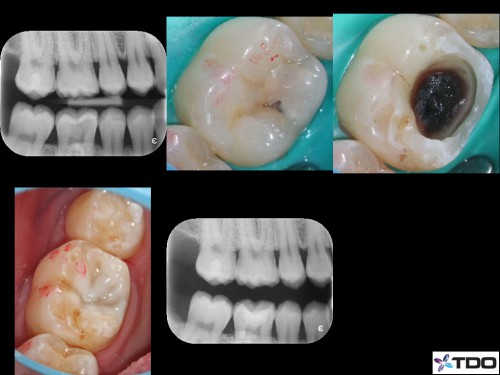

Apexogenesis + Selective Endo

By Siju Jacob / June 27, 2018

Patient was to be reviewed 2 weeks after initial treatment. Turned up after 3 years. […]